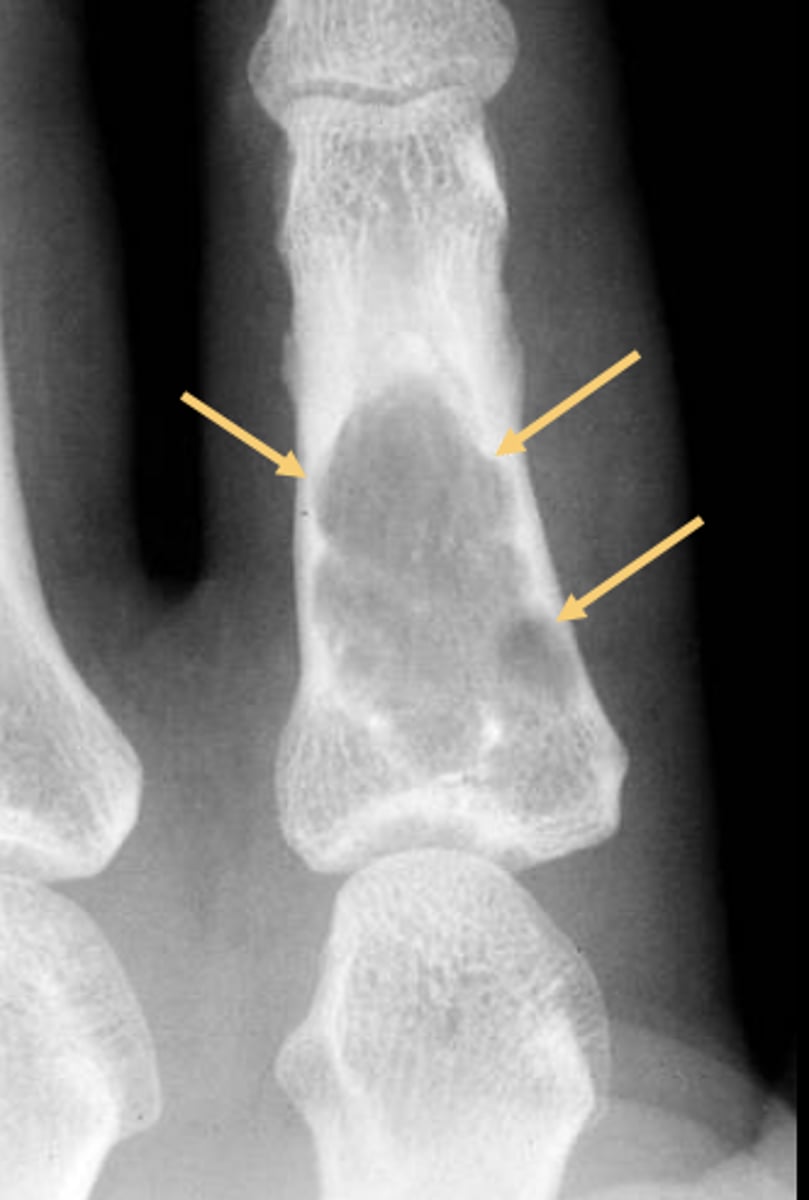

57

New cards

- Solitary

- Eccentric

- Geographic

- Multiloculated

- No malignant transformation

State the radiographic features of non-ossifying fibroma

<p>State the radiographic features of non-ossifying fibroma</p>

58

Geographic bone blister

ID radiographic feature of non-ossifying fibroma indicated by top arrow

<p>ID radiographic feature of non-ossifying fibroma indicated by top arrow</p>

59

Septations

ID radiographic feature of non-ossifying fibroma indicated by bottom arrow

<p>ID radiographic feature of non-ossifying fibroma indicated by bottom arrow</p>

60